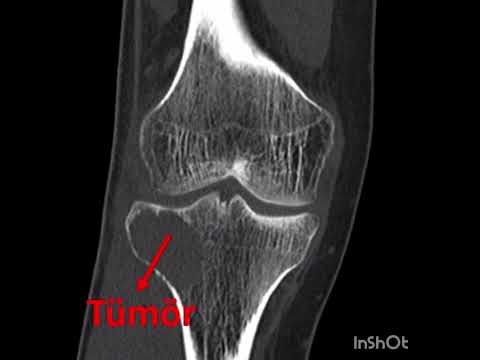

Kemik tümörlerinin tanısında basit röntgenler çok önem taşır ve doğru şekilde değerlendirildiğinde yeterli olabilir. Ancak kötü huylu olabileceği düşünülen ya da yumuşak doku tümörlerinde mutlaka MR çekilmelidir. MR kontrastlı olmalı ve yeterli kalitede olacak şekilde çekilmelidir. Aksi halde hasta tekrar MR çektirmek zorundadır. Kemik tümörlerinde zaman zaman bilgisayarlı tomografiden de yararlanılır. Ayrıca kemik taraması isteniyorsa, ya da tümörün diğer kemiklere yayılıp yayılmadığının anlaşılabilmesi için kemik sintigrafisi de önem taşır. PET ise son derece özel bir görüntüleme yöntemi olup henüz tanı almamış hastalar için yeri yoktur.